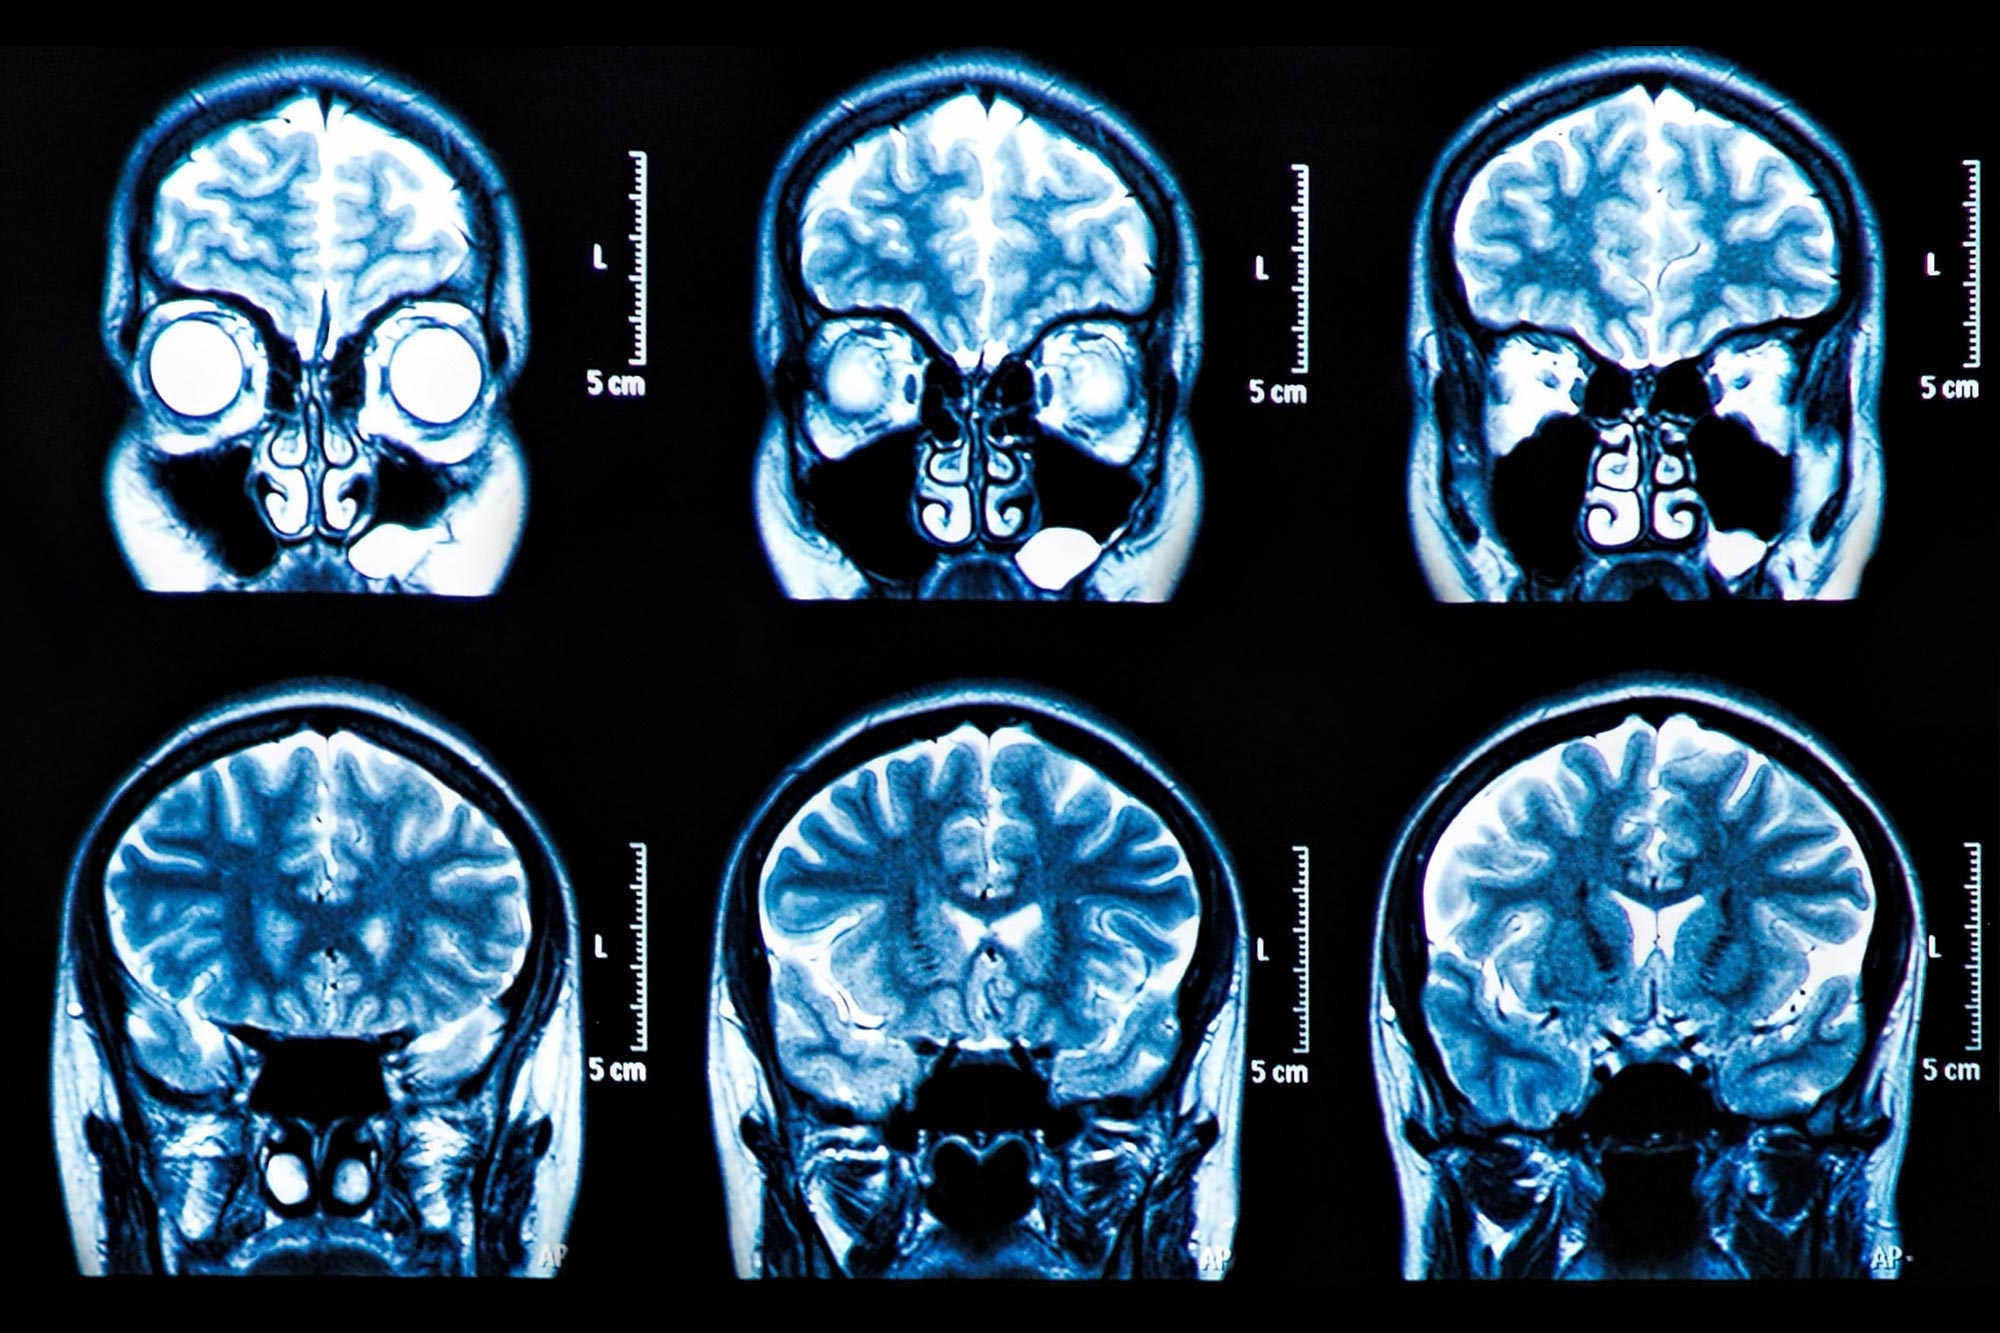

Adhd Brain Vs Normal Brain Scan

Adhd Brain Vs Normal Brain Scan

ADHD Brain Vs Normal Brain Functions Differences More

Pin On ADHD SPD Dyslexia Autism

Discover the beauty of perennial flowers throughout the year with our comprehensive Perennial Monthly Bloom Calendar From the elegance of Lupines in summer to Bee Balm in the Adhd Brain Adhd Vs Normal Brain Brain Patterns Put Adhd In Focus Australasian

ADHD Brain Differences Stuff4Educators

Adhd Vs Normal Brain Brain Patterns Put Adhd In Focus Australasian

Compare Normal Vs ADHD Brain YouTube

Adhd Brain Vs Normal Brain Scan

Brain Markers Of ADHD Identified In Children s MRI Scans